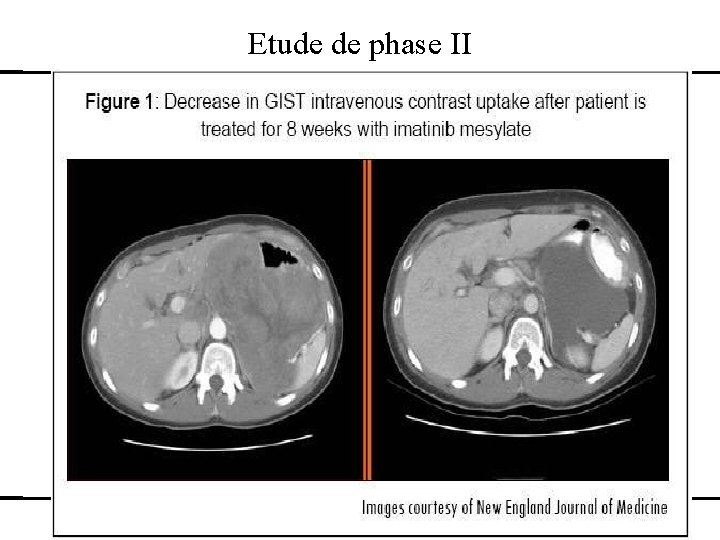

Etude de phase II Développement d’un médicament – études cliniques – exemples des anti-cancéreux L 2 : 17 -10 -2011

Etude de phase II Il n’y a pas de traitement efficace connu dans cette situation On considère qu’un traitement donnant moins de 10% de réponse objective serait décevant. P 1=15% et p 0=10% Risque Alpha de 5% et risque Béta de 10%. Nombre de sujets nécessaires 50 Plan en une étape Un traitement inefficace est rejeté si ≥ 7/50 Développement d’un médicament – études cliniques – exemples des anti-cancéreux L 2 : 17 -10 -2011

Etude de phase II Traitement inefficace (10%) 7/50 Réponses ou moins Observé (19%) 9/50 réponses objectives L’évaluation de ce traitement peut se poursuivre si profil de tolérance acceptable Développement d’un médicament – études cliniques – exemples des anti-cancéreux L 2 : 17 -10 -2011